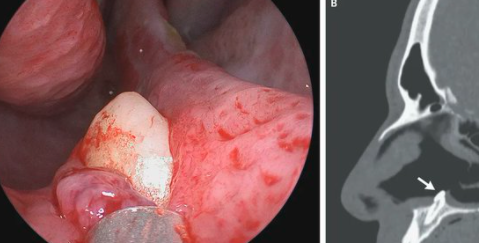

Fue al médico porque tenía dificultad para respirar: descubrieron que en la nariz le crecía un diente